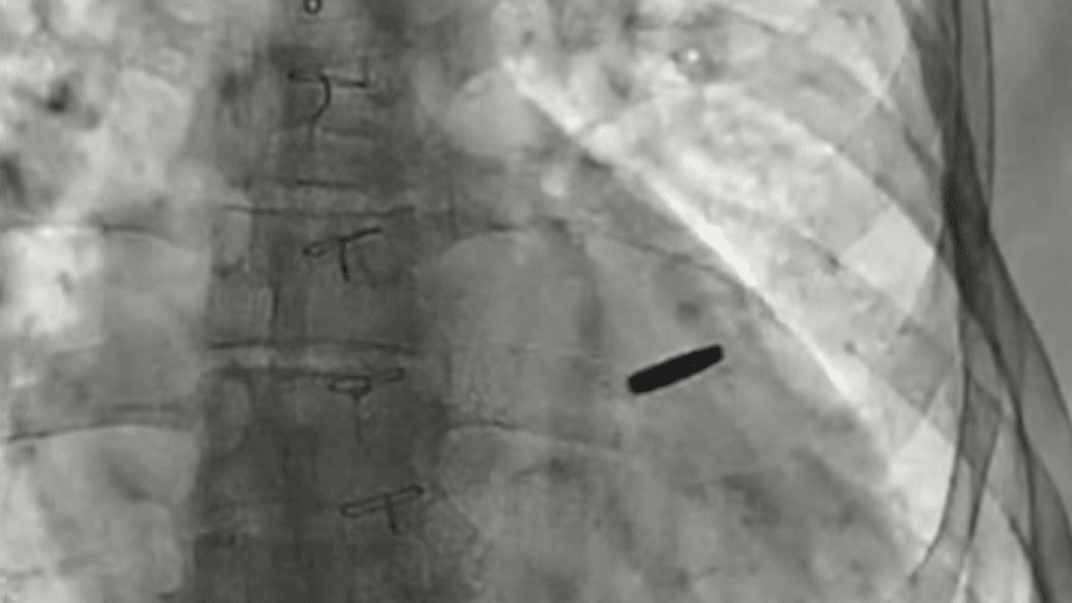

З серця звільненого з російського полону українського парамедика дістали кулю, з якою він прожив три роки.

«Три роки він був з цієї кулею, прожив. На щастя, вона нічого не пошкодила, зараз ми її видалили, пощастило хлопцю», — наголосив Тодуров.